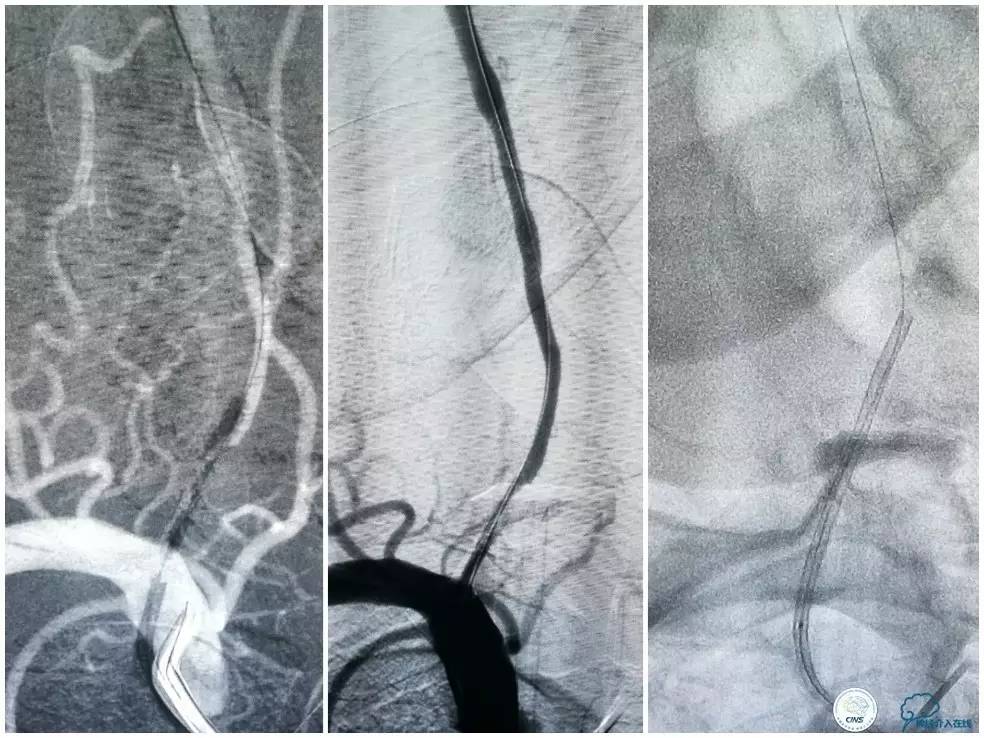

Transend(0.014″300cm)微导丝+Echelon-10微导管,小心通过右椎动脉V4段病变后置于右大脑后动脉P1段(图13)。

图13

Gateway球囊(1.5mm×15mm)于狭窄段扩张后放置Wingspan支架(2.5 mm×15mm),撤出微导丝后造影,局部狭窄率50%,支架内中远段见细小充盈缺损,考虑急性血栓形成,予以欣维宁5ml动脉内缓慢注射未见好转(图14)。

图14

遂再次将Transend微导丝送至右大脑后动脉P1段,使用Gateway球囊(2.0mm×15mm)于支架最狭窄处后扩张(图15)。

图15